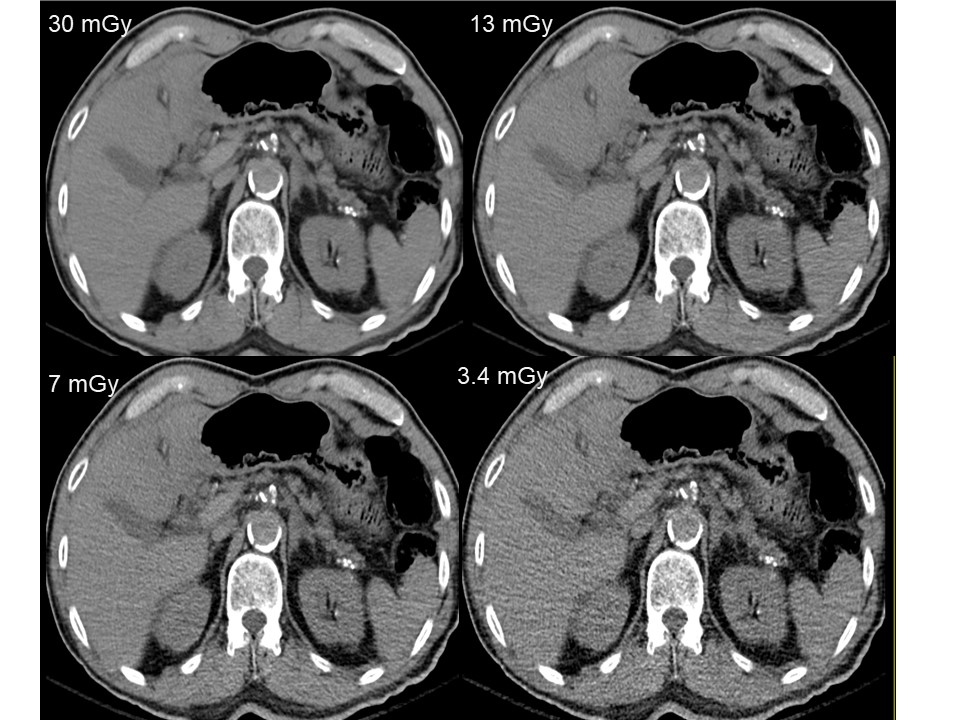

There are variations in scan practices and radiation doses associated with computed tomography (CT) performed in patients with urinary stones and hematuria. Studies have shown that it is possible to reduce radiation doses for these indications without affecting the diagnostic information available from CT images. This presentation will review the existing literature on optimizing CT for urinary stones and hematuria and discuss practical strategies on optimizing scan protocols on various CT platforms.